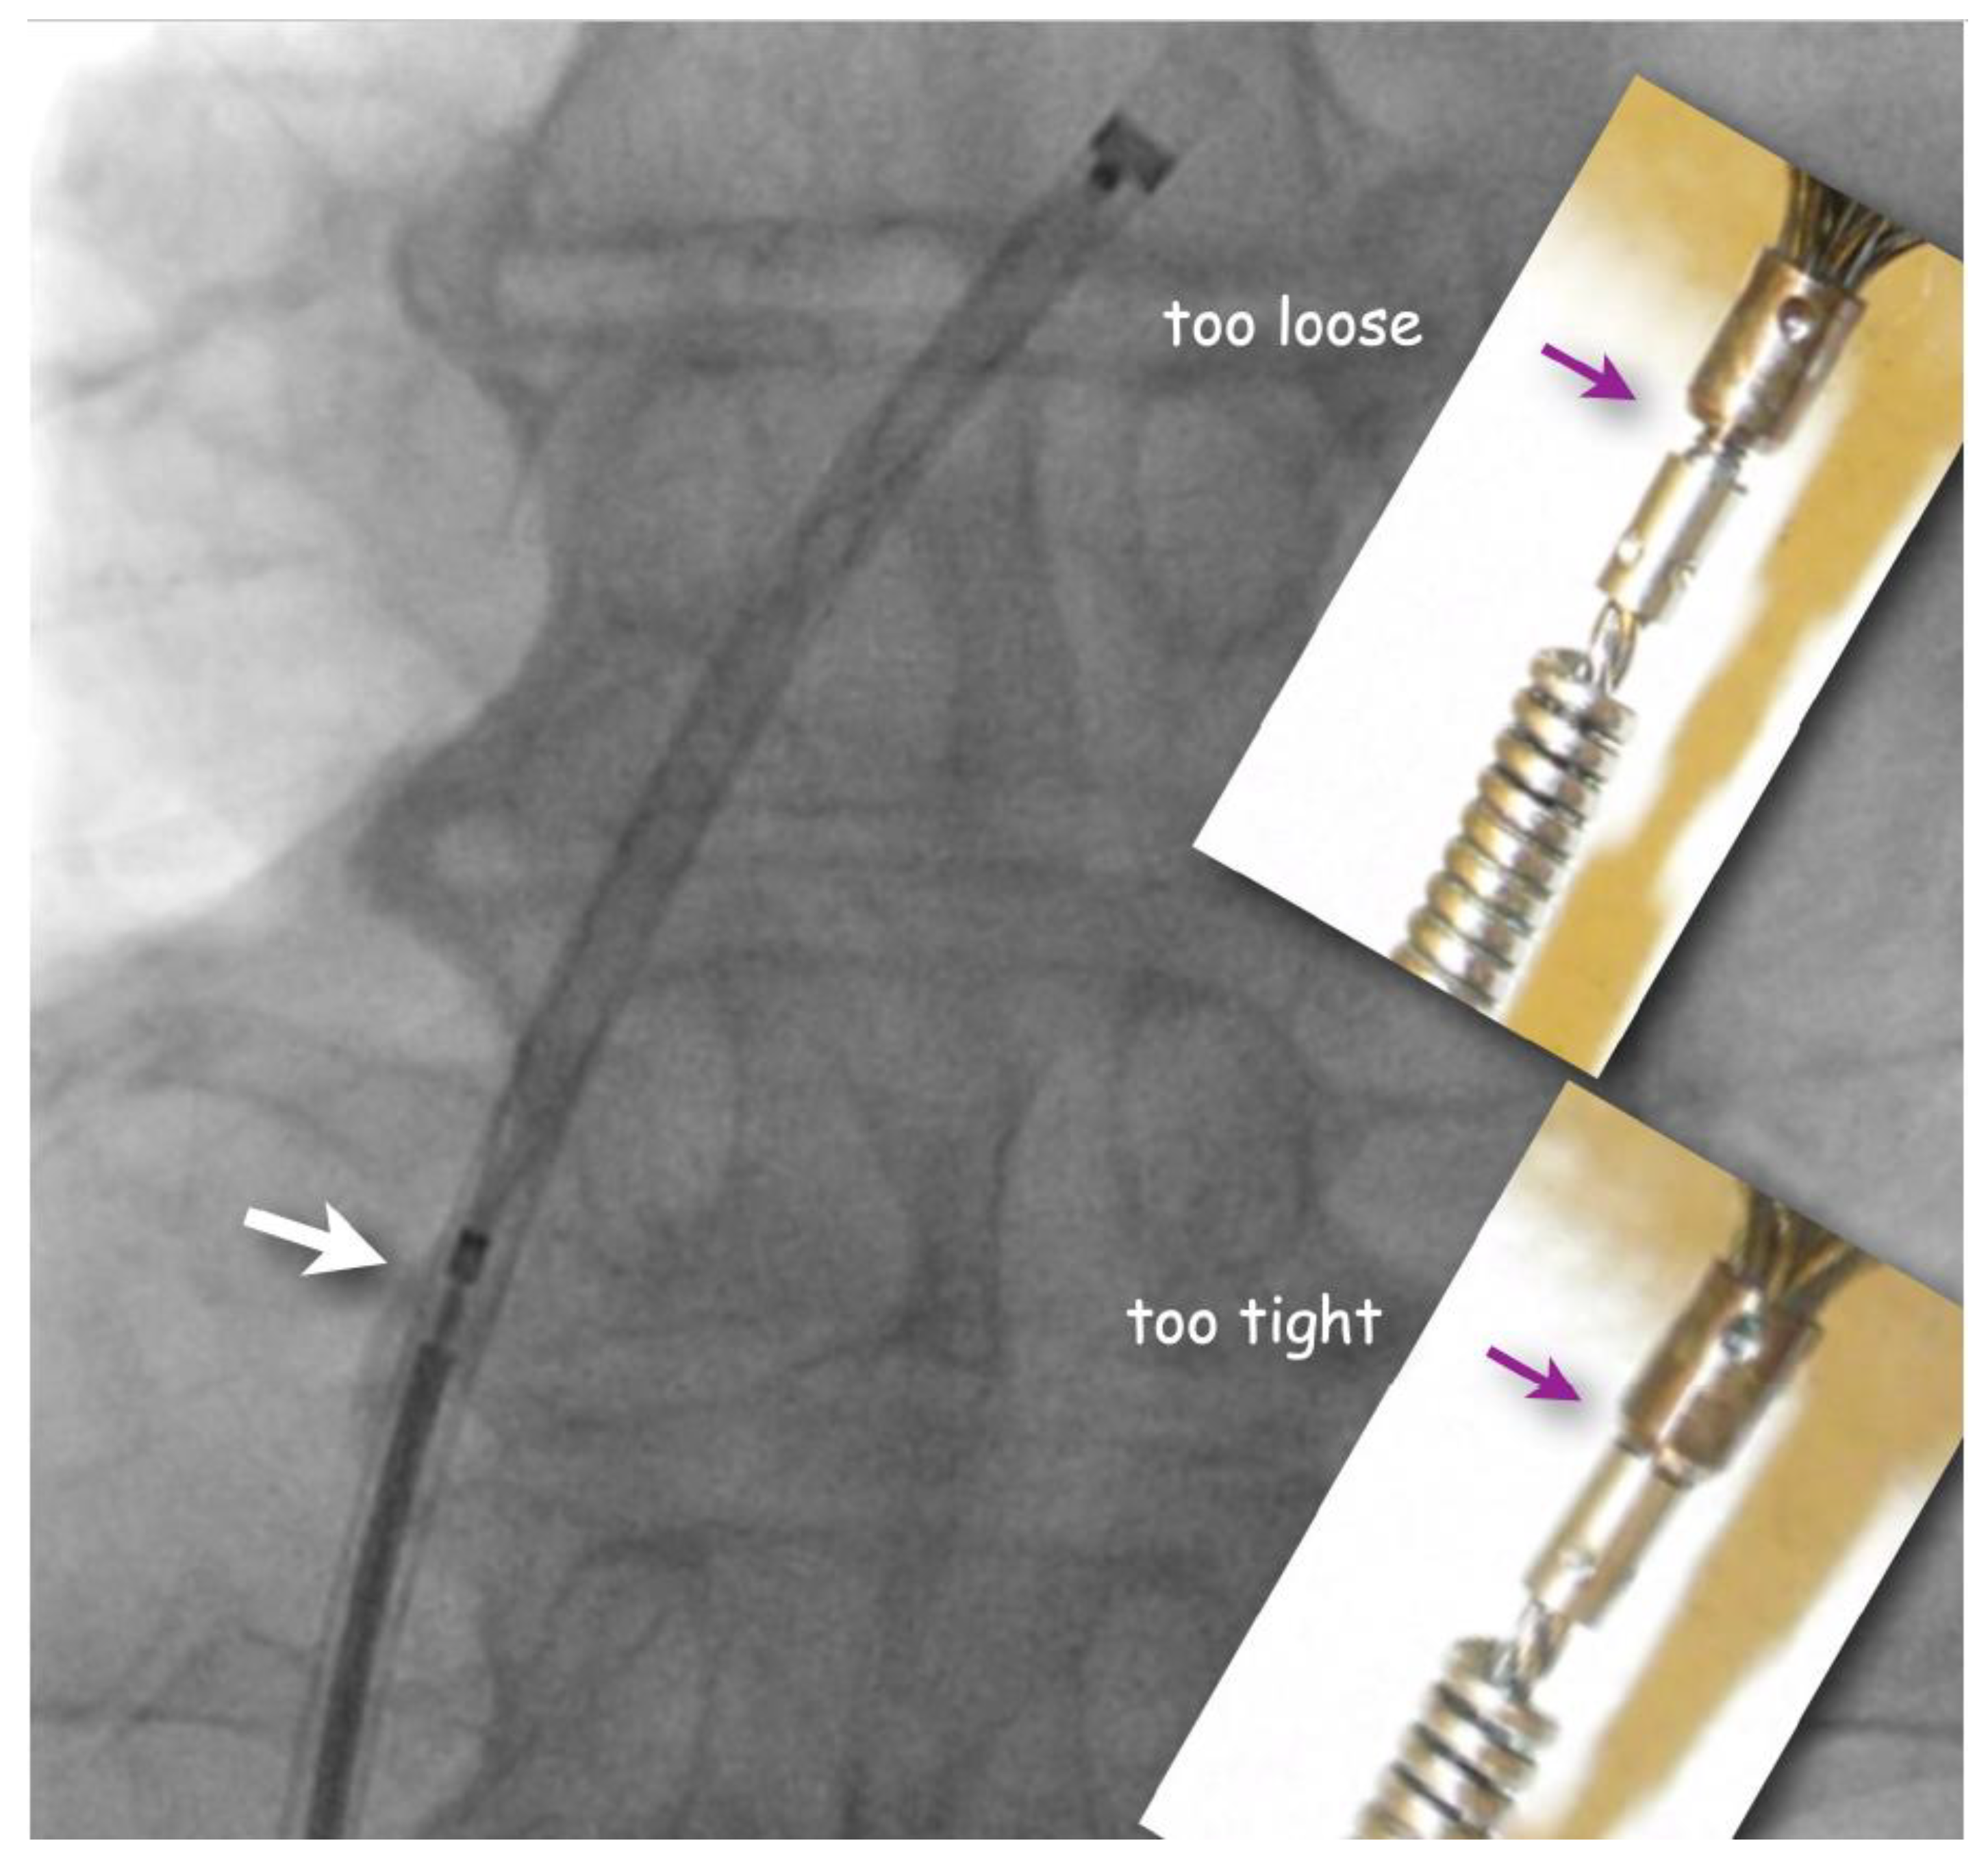

The flushed short loader sheath containing the selected preloaded occluder with its tip just peeking out is connected to the backbleeding sheath and the device is advanced to the distal tip of the sheath without any simultaneous flushing. Before exiting the sheath, it is made sure that the screw used for fixing the original Amplatzer device and most of its derivatives during delivery is still properly tightened, but not too much. A small gap ought to be visible (Figure 2). If there is no gap, one or two full left (counterclockwise) turns are recommended, during which an unblocking click is usually felt. This assures that the screw is not tightened overly fast so that the occluder would swivel with the loader cable rather than being released when the unscrewing is attempted at the end of occluder positioning. Too generous a gap results from inadvertent partial unscrewing of the occluder on the way up through the sheath. That needs to be corrected with turning right (clockwise) on the loading cable. In the extremely rare case that the screw is seen to be completely disconnected, the device is not implanted but pulled out of the sheath with a snare and reattached properly before reinsertion and implantation.

Figure 2.

Fluoroscopic check of correct attachment of Amplatzer(-like) occluders (frontal view). A small gap (white arrow) between pusher screw collar and screw nut on the device guarantees that the occluder is still safely attached but will be easily detachable once positioned. The inserts show screw positions that should be corrected by turning the pusher cable either clockwise (if too loose) or counterclockwise (if too tight) before advancing the occluder out of the sheath.